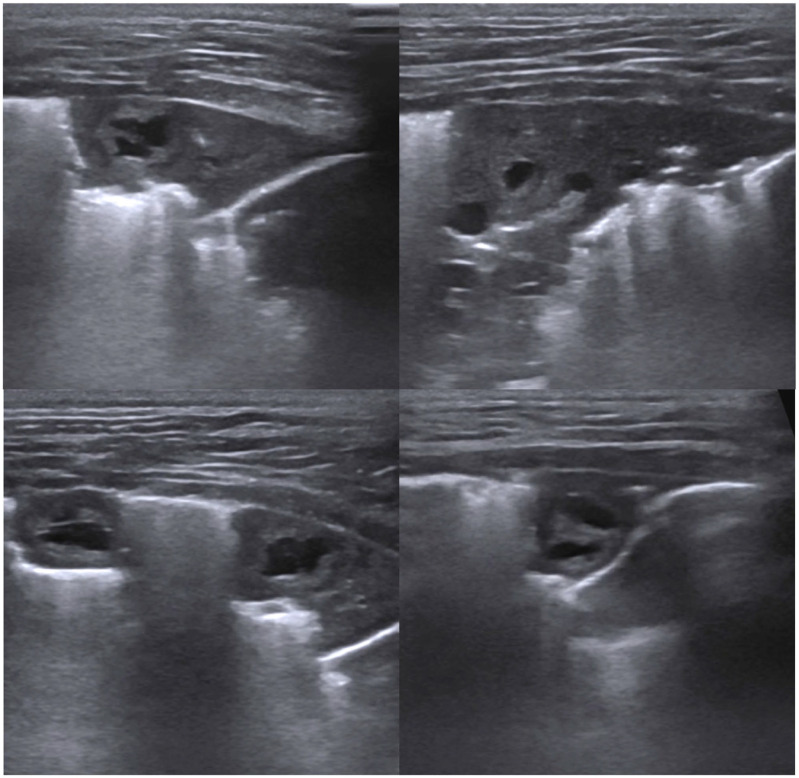

病例总结:一只1岁的完整雌性家养短毛猫,因呼吸窘迫和呼吸急促加重而接受评估。这只猫在4天前被主要临床医生诊断为自发性气胸,并接受了治疗性胸穿刺治疗。在体格检查中,患者表现出肺音减少,呼吸急促和呼吸力度增加。复发性自发性气胸经胸片证实,并重复治疗性胸穿刺。胸穿刺后肺超声显示肺实变、肺结节及多发囊肿样病变,回声壁不规则增厚,中心无回声。胸部重复x线片显示弥漫性中度支气管间质型伴多灶性软组织结节。彻底的粪便检查显示卵子与肺吸虫种类相似,随后的分子分析证实了威氏肺吸虫。猫最初仅用芬苯达唑治疗,结果改善有限,自发性气胸复发。芬苯达唑联合吡喹酮的第二个疗程导致临床改善。这只猫没有任何临床症状,病情很好,在诊断后2年的胸片上没有可识别的肺结节。相关性和新信息:本报告描述了一种新的囊肿样肺超声发现,其特征是回声壁不规则增厚,中心无回声,伴有P westermani感染,表现为复发性自发性气胸。该报告还强调了一种成功的治疗方法,可以长期解决问题。这种新的肺部超声发现的识别有助于早期诊断和治疗猫的肺吸虫感染,特别是对那些出现呼吸窘迫和气胸的猫。

Case summary: A 1-year-old intact female domestic shorthair cat presented for evaluation of worsening respiratory distress and tachypnoea. The cat had been diagnosed with spontaneous pneumothorax 4 days earlier by the primary clinician and treated with therapeutic thoracocentesis. On physical examination, the patient exhibited decreased lung sounds, tachypnoea and increased breathing effort. Recurrent spontaneous pneumothorax was confirmed via thoracic radiography, and therapeutic thoracocentesis was repeated. Lung ultrasound performed after thoracocentesis revealed lung consolidation, pulmonary nodules and multiple cyst-like lesions with irregularly thickened echogenic walls and anechoic centres. Repeat thoracic radiography showed a diffuse moderate bronchointerstitial pattern with multifocal soft tissue nodules. A thorough faecal examination revealed ova resembling those of Paragonimus species, and subsequent molecular analysis confirmed Paragonimus westermani. The cat was initially treated with fenbendazole alone, which resulted in limited improvement and recurrent spontaneous pneumothorax. A second course of fenbendazole combined with praziquantel led to clinical improvement. The cat remained free of clinical signs and was doing well, with no identifiable lung nodules on thoracic radiography 2 years after diagnosis.

Relevance and novel information: This report describes a novel cyst-like lung ultrasound finding characterised by an irregularly thickened echogenic wall and anechoic centre, associated with P westermani infection in a cat presenting with recurrent spontaneous pneumothorax. The report also highlights a successful treatment approach resulting in long-term resolution. The identification of this novel lung ultrasound finding can facilitate early diagnosis and treatment of Paragonimus species infection in cats, especially for those presenting with respiratory distress and pneumothorax.